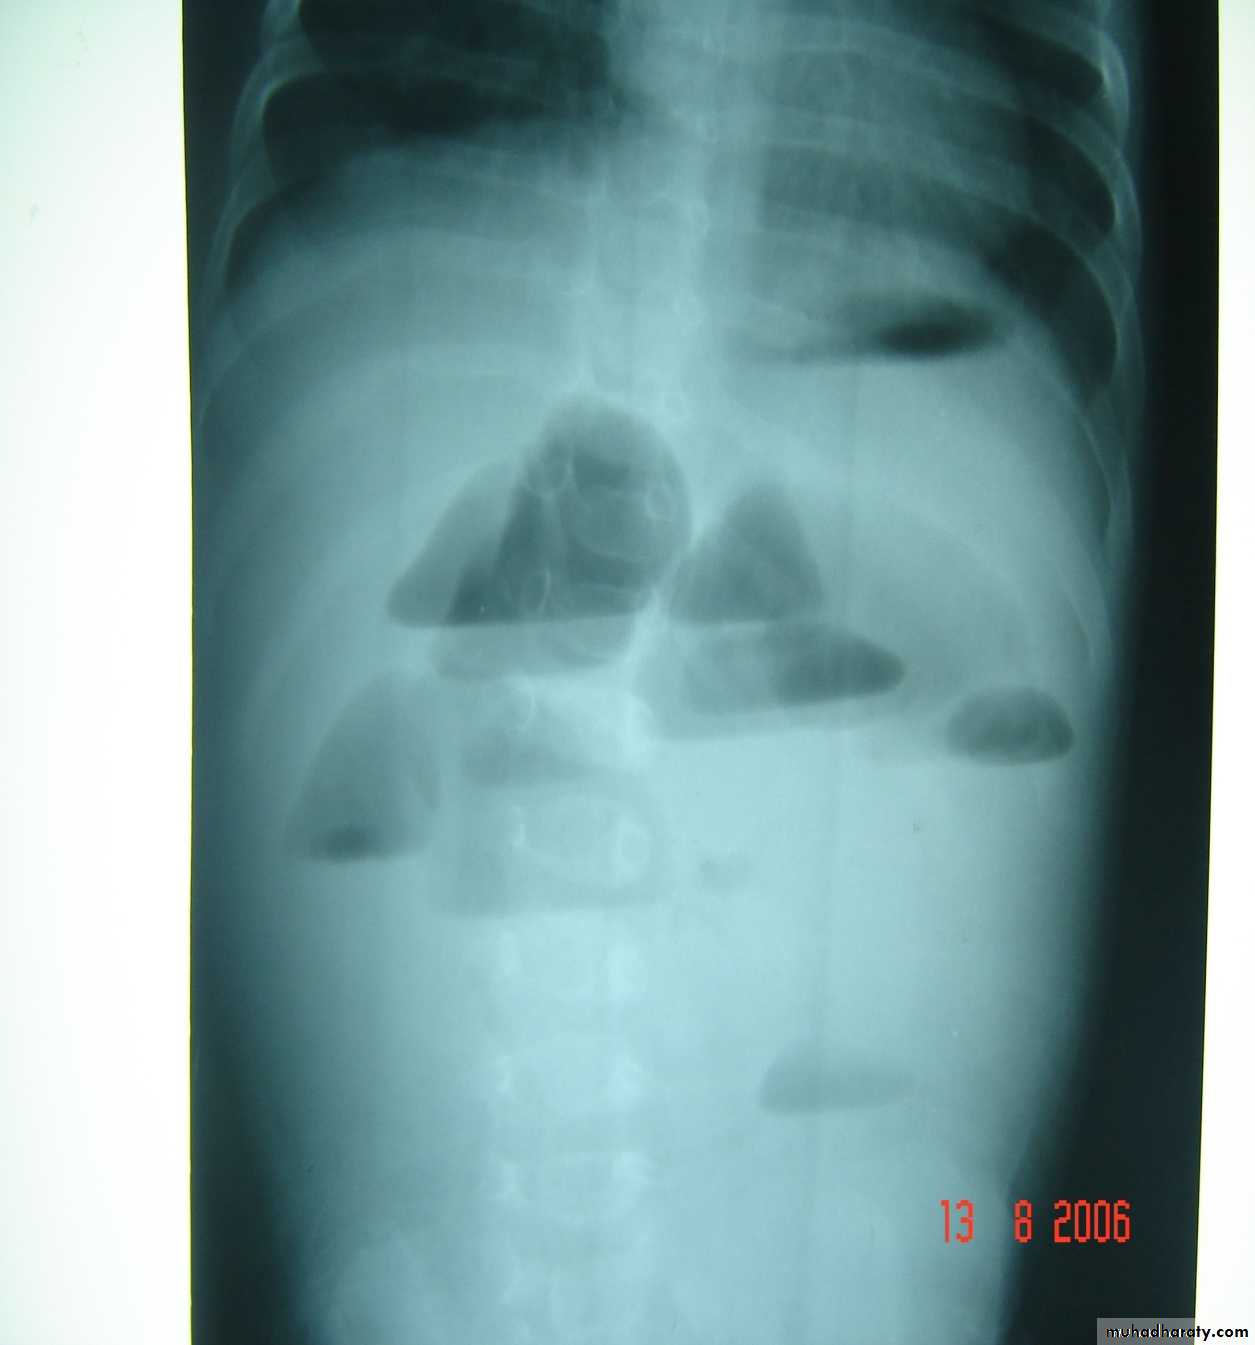

Bowel Obstruction